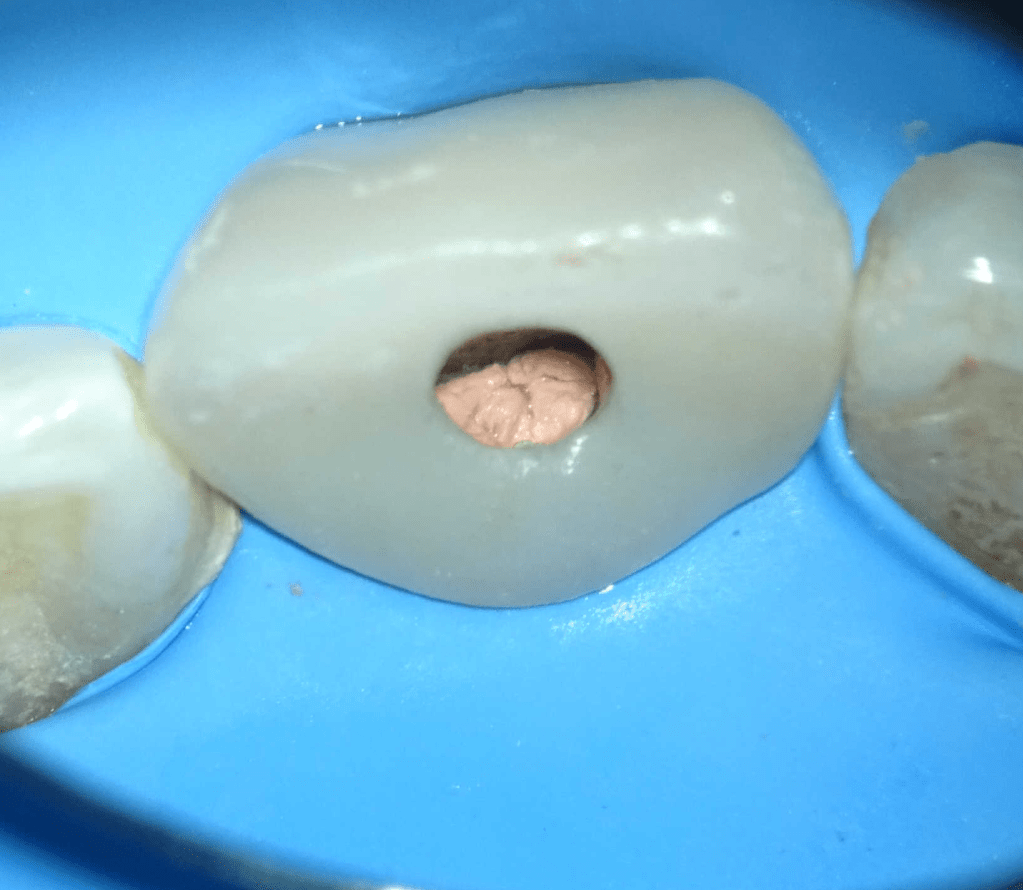

Pulpotomía biodentine + reco preendio